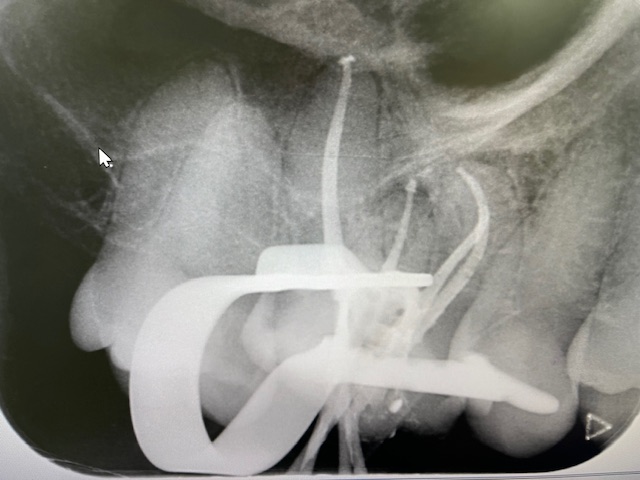

Unlike most general dentists, at Allure Dental, we utilise a high-magnification operating microscope. This increases the dentist’s ability to visualise the inside of the tooth, locate and then use the instrument for complex canal formations.

• Thorough cleaning, shaping, and disinfection of the root canal system.

• Sealing the canals with biocompatible materials to prevent reinfection.